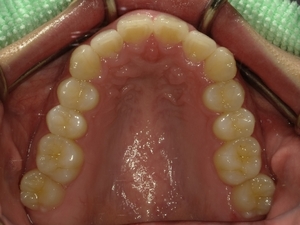

ガタガタとした歯並びや八重歯(叢生)CASE51